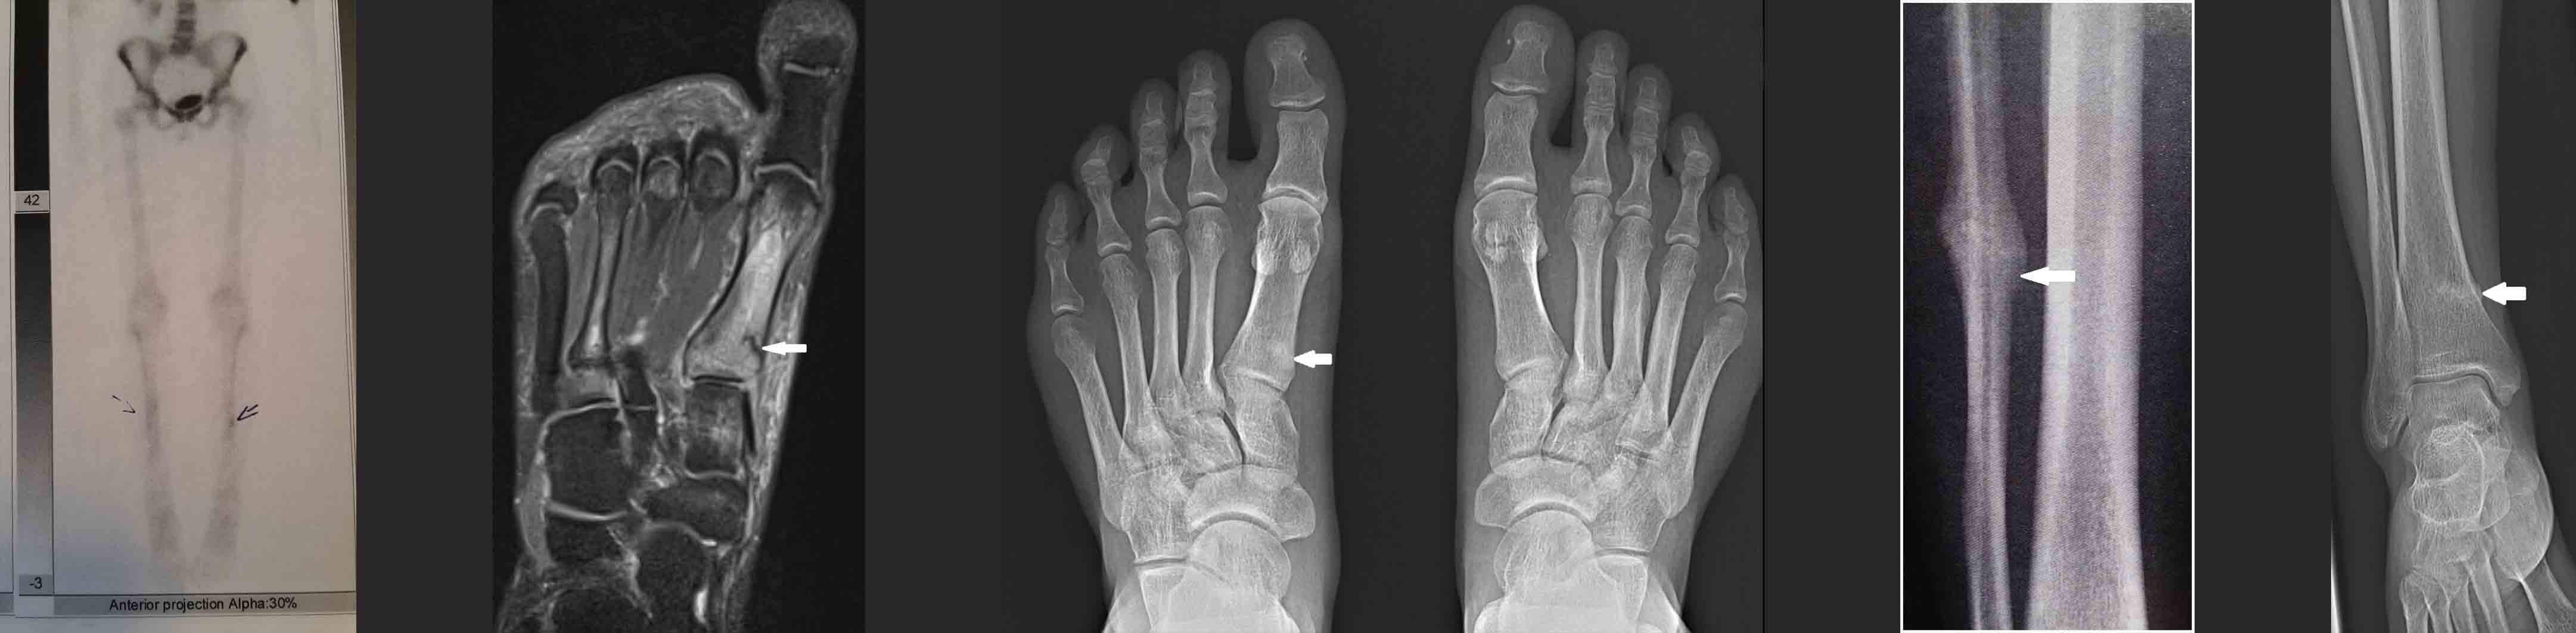

Stress Fracture – Diagnosis

Diagnosis of a stress fracture begins with a medical history and clinical examination conducted by a specialist. Imaging tests, such as X-rays and ultrasounds, are the next steps. In early stages, a stress fracture may not be visible on an X-ray. For more challenging cases (e.g., involving the pelvis or spine), further diagnostics, such as magnetic resonance imaging (MRI) or bone scintigraphy, may be required.

Common Locations of Stress Fractures

- Tibia – approximately 30% of cases,

- Navicular bone (tarsal bone) – approximately 20%,

- Metatarsal bones – approximately 20%,

- Femur – approximately 15%,

- Fibula – approximately 10%,

- Pelvis – approximately 5%.